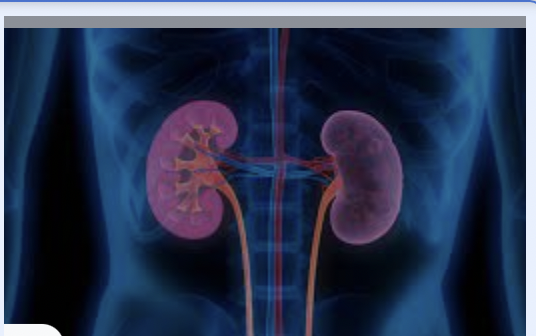

Kidney stones are known for the most excruciating pain. The most common, stones are calcium oxalate (roughly 80%) while 5-10% are uric acid crystal. understanding the type of stone is the key to prevent it from re-forming.

Factors involve in formation of kidney stones